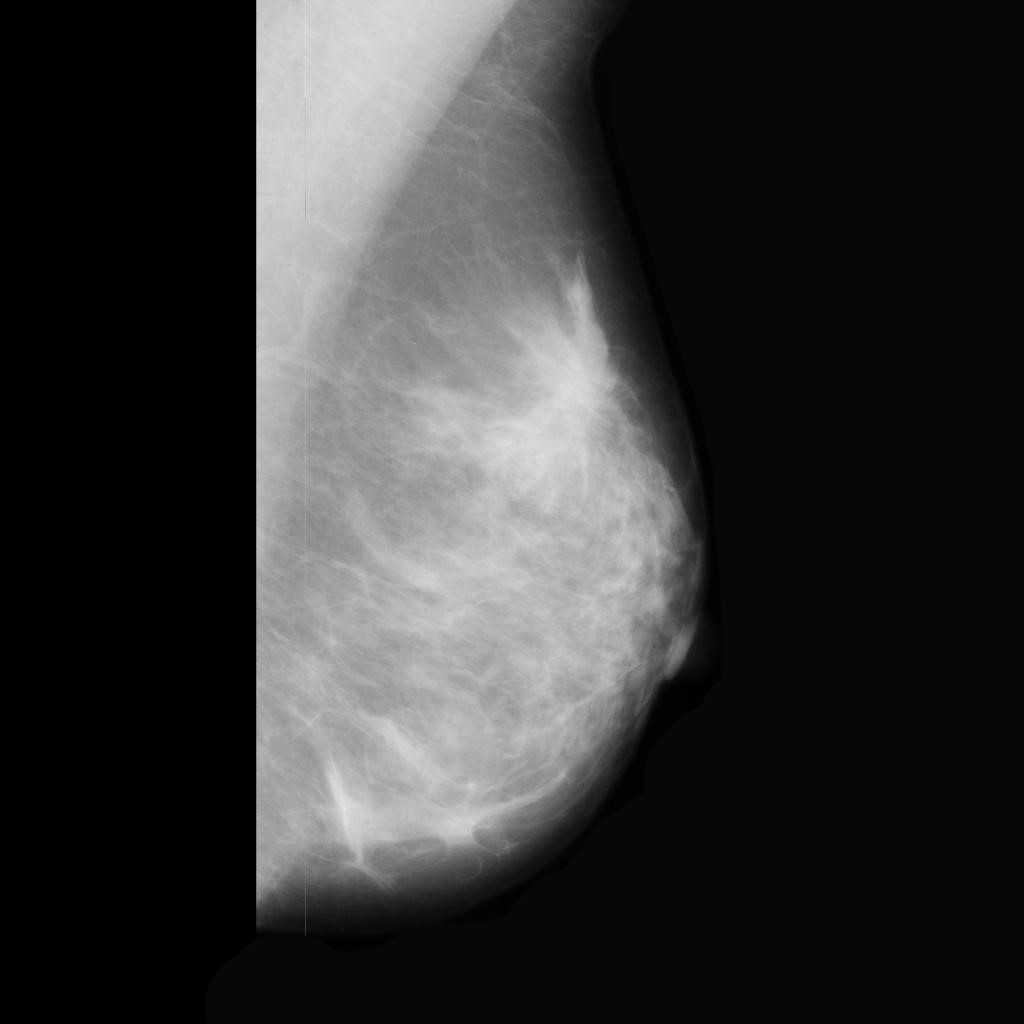

malignant